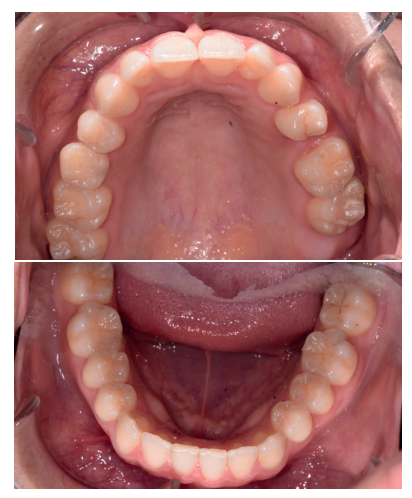

Se presenta un caso clínico de una mujer de 20 años de edad, que acudió remitida por su ortodoncista para la extracción de un premolar retenido maxilar, en posición invertida, previo a la realización de tratamiento ortodóntico. Se realizó la Historia Clínica de la paciente, que no presentó antecedentes médico-quirúrgicos de interés, alergias medicamentosas conocidas ni hábitos nocivos. A la exploración extraoral no se apreció ningún dato relevante. A la exploración intraoral, la paciente presentó la ausencia en boca del segundo premolar superior izquierdo y la presencia de los terceros molares inferiores retenidos (Figuras 1, 2 y 3).

A la exploración radiográfica mediante radiografía panorámica se apreciaron ambos terceros molares inferiores retenidos, en una posición mesioangular, los superiores retenidos en posición vertical y la presencia de un premolar maxilar retenido, en posición invertida, en el segundo cuadrante (Figura 4).